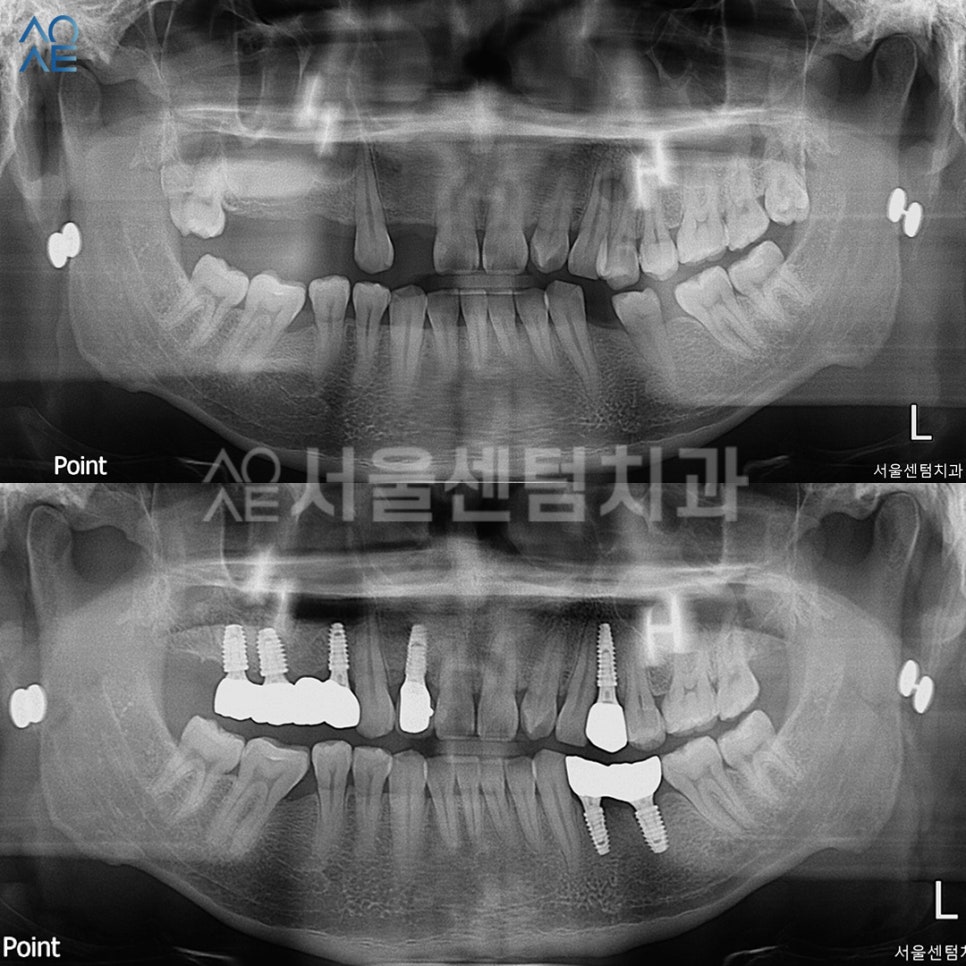

보철물 영구 접착 후 3개월 검진에서

촬영한 사진과 비교입니다.

기간 알기 쉽게 사진마다

촬영한 날짜를 표시해두었습니다.

다행히 불편한 점 없다고 하셔서

6개월 검진 때 뵙기로 했습니다.

임플란트 총 7개와 사랑니발치 등

정말 많은 치료를 진행하였는데요.

다행히 진료일정에 잘 맞춰주어서

기간 딜레이 없이 잘 마무리 되었습니다.